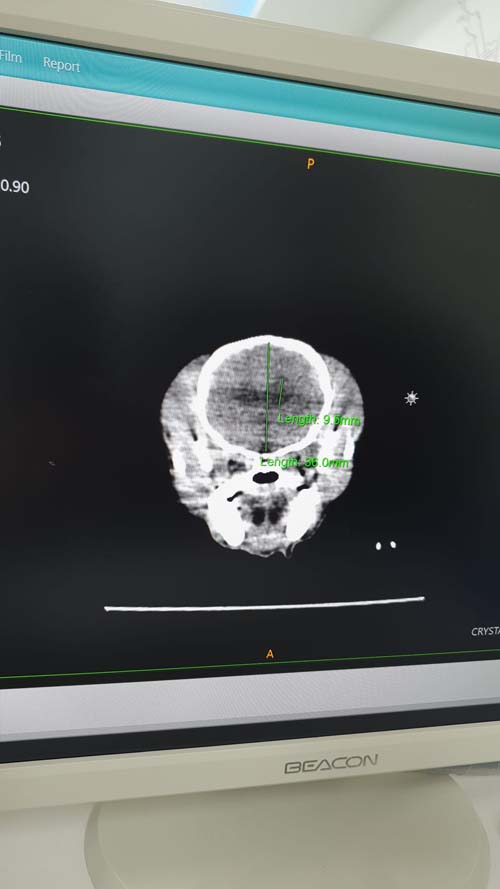

หลายๆ บ้าน ib มาถามผลการ CT Scan แชลมาล ขอบคุณมากนะคะ มาค่ะ มารีวิวเป็น Q&A ว่าทำไมต้องซีที มันจำเป็นมั้ย และทำยังไงบ้างนะคะ เนื้อหาเต็มๆ และยาวมากๆ อาจจะเครียดนิดนึงนะคะ ใครขี้เกียจอ่าน ข้ามไปดูคลิปได้เลยในคอมเม้นต์ค่ะ ขอบคุณน้องมาร์ช Marsh The Happy Dog ที่ให้ข้อมูล มาให้กำลังใจด้วย ช่วยถ่ายคลิปให้ แถมแจกขนมจากเจอร์ไฮปลอบใจอีกต่างหาก เลิฟ Q1: ทำไมคิดมาทำ CT Scan A1: แชลมาล มีอาการไม่สบายตัว เหมือนจะเจ็บ หรือปวด เล็กๆ ไม่ที่หลังก็ท้อง อาการคือ เวลากินเสร็จ จะตัวสั่น ประมาณ 5 นาทีก็หาย ไม่ยอมเดิน ไม่ยอมยกขาหน้า ไม่ขึ้นสเต็ปเตี้ยๆ ที่เคยขึ้น แต่ไม่มีการเกร็งตัว, โก่งตัว และยังวิ่งเล่น เห่า กิน ถ่ายปกติ เป็นประมาณ 2-3 วันก็หายปกติ แล้วอีกเดือนมาเป็นใหม่ พาไปหาหมอ หมอ 3 คนบอกว่าเป็นปวดหลัง อาจจะจากกระดูกงอก หรือกระดูกทับเส้น ตามวัย อีกคนบอกว่าอาจจะปวดท้อง ถ้าจะให้รู้แน่ๆ ก็ต้องทำ CT Scan จะได้ดูทั้งหลังและท้องในทีเดียว Q2: CT Scan ต่างจาก X-Ray ยังไง A2: เป็นการใช้รังสี X ในการสแกน เหมือนกัน แต่ซีที ทำได้ละเอียดและครอบคลุมมากกว่า สามารถจำลองภาพเป็น 3 มิติให้เห็นพื้นผิวได้ชัดกว่า ทำทีเดียวได้ทั้งร่าง ทุกส่วน ทุกอวัยวะ ถ้า เอ็กซ์เรย์ จะถ่ายได้ทีละส่วน Q3: ทำไมเลือกทำที่ Crystal CT Scan Center A3: การทำซีที คือการต้องนอนให้นิ่งที่สุด เพื่อเวลาสแกน จะเห็นภาพได้ชัด ถ้าหากมีการสั่น ขยับ เคลื่อนไหว ภาพที่ได้จะเบลอๆ เป็นควัน ทำให้วิเคราะห์ผลยาก และอาจจะคลาดเคลื่อน ในปัจจุบัน สำหรับสัตว์ เลยต้องวางยาสลบ ซึ่งแชลมาลมีภาวะโรคหัวใจ เสี่ยงกับการวางยาสลบ แล้วจะไม่ฟื้น ที่ Crystal CT Scan Center เค้าเป็นเครื่องแบบใหม่ ที่มี 128 สไลด์ (จำนวนสไลด์ ยิ่งมาก เครื่องจะยิ่งทำงานได้เร็ว) ทำให้แค่วางยาซึม ไม่ต้องวางยาสลบ เราเลยเลือกที่นี่ค่ะ (ตอนที่สแกน ถามเจ้าหน้าที่ของ บ.เครื่องที่อยู่ด้วย เค้าบอกว่า สำหรับ รพ.ส. ตอนนี้ยังมีแค่ที่นี่ที่เดียว ที่ใช้เครื่องรุ่นนี้ค่ะ) Q4: ทำยังไงบ้าง เห็นอะไรบ้าง A4: ตอนแรกก็คุยกับคุณหมอก่อนว่า เรามีอาการยังไงมา อยากตรวจอะไร คุณหมอแนะนำยังไงบ้าง แชลมาลกับชมิล มีคุณหมอประจำอยู่ 3 ที่ คือที่ รักษาทั่วไป ที่คริสตัลเพ็ท รักษาตา และฉุกเฉินตอนกลางคืน ที่รัตนาธิเบศร์ สาขาเกษตร-นวมินทร์ รักษาหัวใจ ที่ ประศุอาทร มหิดล ถ้าไม่ได้เป็นคนไข้ที่คริสตัลเพ็ท ก็มาสแกนได้นะคะ ไม่จำเป็นต้องเป็นคนไข้ที่ คริสตัลเพ็ทเท่านั้นค่ะ ของเคสแชล คุณหมอบอกอยากสแกน หัว คอ หลัง ปกติถ้าสแกน 1 จุด ราคา 3,500 บาท สแกนทั้งตัว ราคา 5,500 บาท ถ้าจะดู 3 จุด ก็สแกนทั้งตัวไปเลย แป๊บเดียว ตัวจิ๋วเดียว คุณหมอให้ลองไปนั่งที่เครื่องแล้วเลื่อนไปมา ว่าไหวมั้ยถ้าไม่วางยา แต่แชลผู้ซึ่งสั่นตลอดเวลา มิไหว เลยวางยาซึมไปค่ะ เพิ่มค่าวางยาซึม 1,000 บาท พอยาซึมเริ่มออกฤทธิ์ ก็พาไปนอนที่เครื่อง มีพี่ๆผู้ช่วยจับ และเริ่มสแกน แป๊บเดียวมากๆ ไม่ถึง 10 นาทีก็เสร็จ ก็ออกมานั่งรอน้ำลายไหลเพราะฤทธิ์ยา แชลใช้เวลาขับยาออกจากตัวค่อนข้างนาน ประมาณ 3 ชม. เพื่อนๆที่เค้าเข้าไปทีหลัง ออกมาก็กินข้าวได้เลยค่ะ การฟื้นจากยา จะแล้วแต่ตัวค่ะ รอคุณหมอเช็คฟิล์ม ตัดเซฟใส่ DVD ให้เรา (ฟรี) ถ้าใครมี USB Drive พกไปด้วยนะคะ คุณหมอเซฟใส่ให้ค่ะ และมีส่งรูปสำคัญๆ ในไลน์ให้ด้วยค่ะ Q5: ผลสแกนเป็นยังไงบ้าง A5: ตอนเข้าไปฟังผล คุณหมอเปิดให้ดูเป็นภาพไล่ไปเรื่อยๆ มันจะเหมือนเราค่อยๆเข้าไปในตัวแชลมาลเลยค่ะ ใช้เวลาตรงนี้เกือบ 50 นาทีแหนะค่ะ ขอบคุณคุณหมอมากๆ ที่อธิบายละเอียดมากเลย ก็ไล่ตั้งแต่ รูจมูก เข้าไปในตา กะโหลก หู หลอดลม ปอด หัวใจ ไล่ไประบบทางเดินอาหาร จนถึงมดลูก เห็นกระทั่งตอที่ผูกปิดมดลูกตอนทำหมัน และมาที่กระดูก ซี่โครง ดูช่องว่างระหว่างกระดูก ดูการเสื่อมของกระดูก ดูสะบ้า สะโพก ว่าอยู่ในตำแหน่งดีมั้ย มีเคลื่อน มีอะไรมั้ย ครบเลยค่ะ แชลมาล กระดูกดีมากๆ ทุกอย่างสวยงาม แต่มีเจอ ภาวะน้ำในสมอง และกะโหลกไม่ปิด ถ้าหมอจับคลำ ทุกคนจะบอกว่ากะโหลกปิดค่ะ แต่เพราะสแกนเลยรู้ว่าไม่ปิด และต้องระวังเรื่องการชัก และกระแทกแรงๆ ตะกอนในถุงน้ำดี ต้องเลี่ยงกินมัน งดอาหารที่มีไขมันสูง มาดูสูตรอาหารใหม่ และมีนิ่วในไต ซึ่งคิดว่าเป็นสาเหตุที่ทำให้ปวดค่ะ อาจจะเกร็งไต แล้วมันเลยไปแสดงออกว่าไม่สบายตัว สแกนรอบเดียว เจอ 3 โรคต้องเฝ้าระวัง Q6: ทำไมมีนิ่วในไต แต่ค่าเลือดปกติมาก A6: แชลมาลเพิ่งตรวจเลือดไปตอนสิงหา และตุลา ค่าเลือด ปกติดีทุกตัวค่ะ คุณหมออธิบายว่า ถ้าปกติตรวจเลือดแล้วค่าไตปกติ ไม่สูง หมอจะไม่สั่งตรวจค่าฟอสฟอรัส ค่าการทำงานของไตต่อ เพราะมันยังไม่จำเป็นที่ต้องดู แต่ในกรณีนี้คือ เจอนิ่วจากการสแกน ไตอาจจะยังไม่ส่งผลว่ามีปัญหา แต่เจอเร็ว ก็ต้องตรวจเลือดเพื่อดูค่าฟอสฟอรัส และเช็คฉี่ ว่าเป็นนิ่วประเภทไหน เพื่อรักษากันต่อไปค่ะ Q7: มันดีมั้ย ควรทำมั้ย A7: จากที่ทำมา รู้สึกประทับใจมากค่ะ เพราะหมาพูดไม่ได้ เค้าบอกเราไม่ได้ว่าเค้าเจ็บตรงไหน เจ็บแบบไหน ต้องใช้การสังเกตล้วนๆ การที่สแกนเข้าไปให้เห็นภาพเลย มันก็ตอบเราได้ดี ไม่ต้องมานั่งเดาเอง หยกยังคิดว่า ถ้าเราสแกนปีละครั้งเพื่อเป็นการเช็คร่างกายใหญ่ พร้อมตรวจเลือดด้วย ก็น่าจะดีนะคะ รู้ก่อน รักษาก็ง่ายกว่า เร็วกว่า Q8: เคลมประกันได้มั้ย A8: คุณหมอบอกว่าสามารถเคลมได้ค่ะ แต่แชลมาลอายุเกินทำประกันแล้ว เลยจ่ายเต็ม รอบนี้จ่ายไป 6,500 บาทถ้วน ได้ความโล่งอกว่าเราไม่ได้คิดไปเองว่าหมาเราปวดท้อง (ทั้งๆที่ไม่โก่งตัว) และจะได้รักษาได้เร็ว เพื่อคุณภาพชีวิตที่ดีของเด็กๆ ค่ะ มีคลิปผลการสแกนอยู่ในคอมเม้นต์นะคะติดต่อสอบถามนัดหมาย @CrystalCTscan